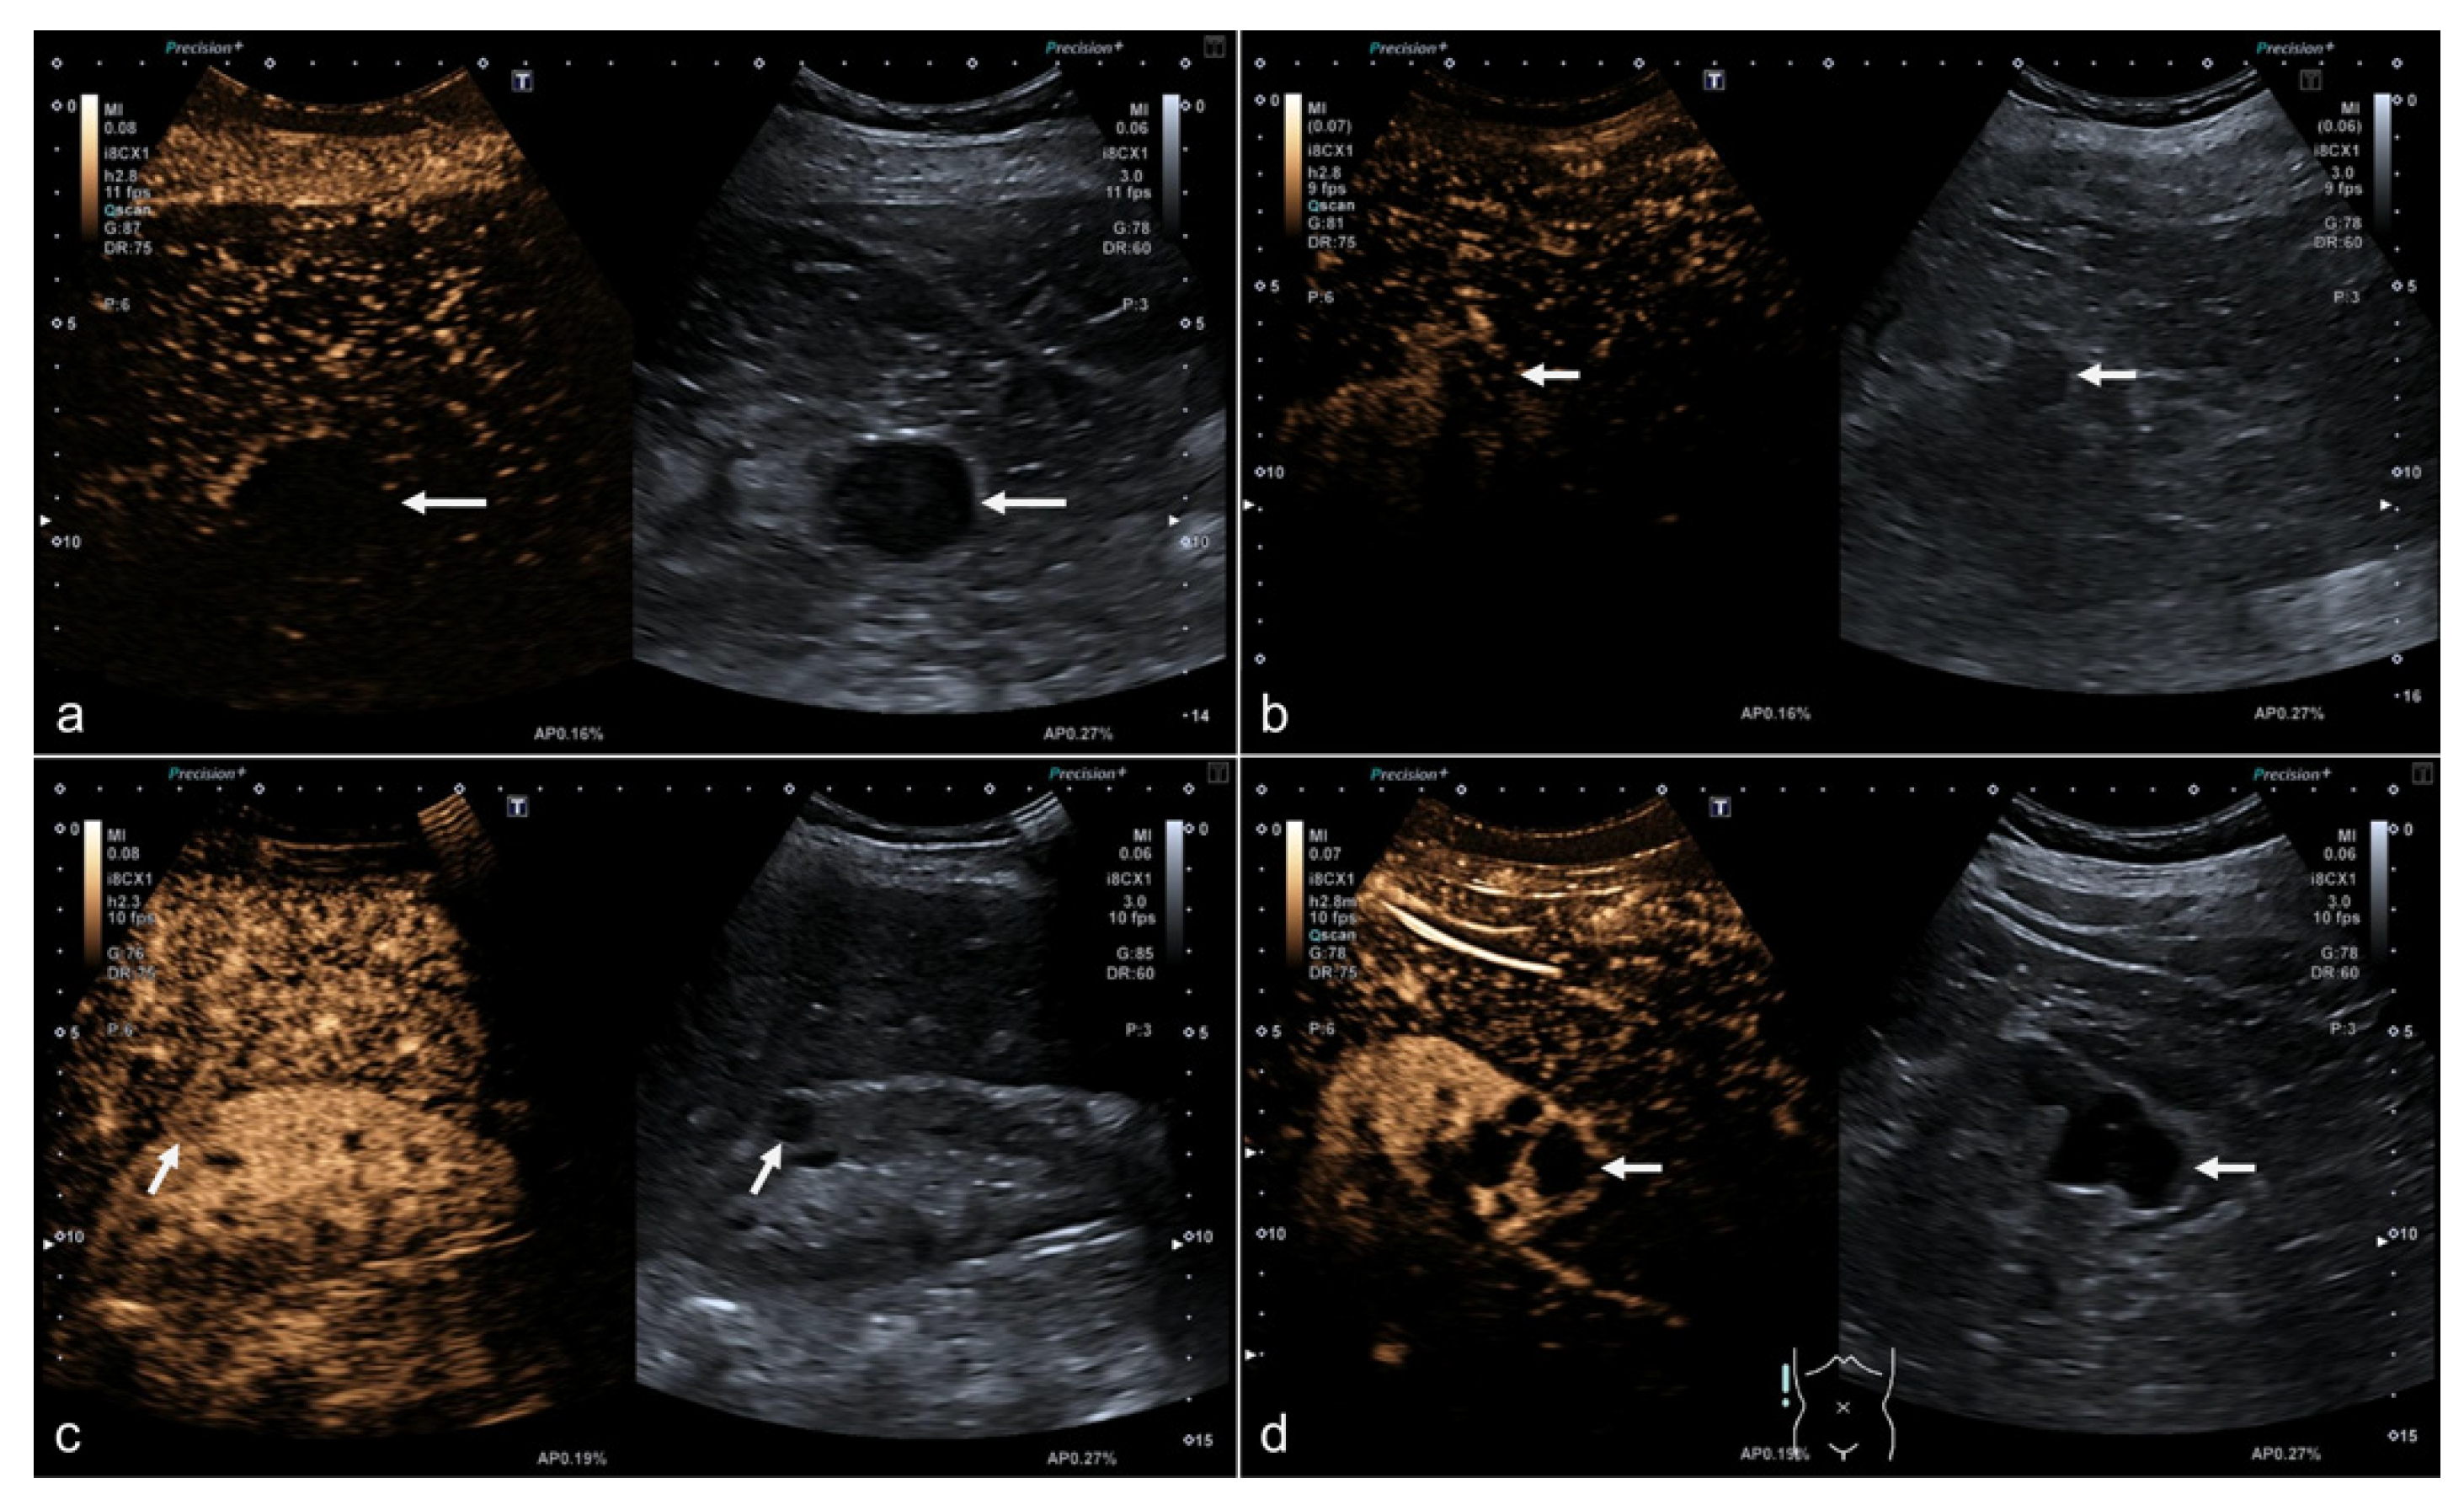

2.2. CEUS Examination

2.3. Assessment of Image Quality